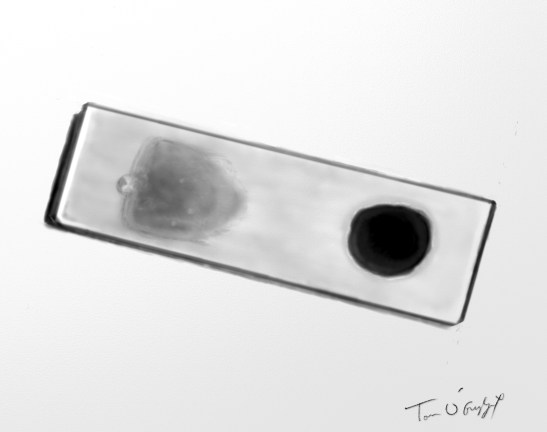

frottis sanguin à gauche et goutte épaisse à droite sur la même lame pour le diagnostic de paludisme au microscope

Publié le 3 décembre 2015 à 1610 × 1274 dans Paludisme grave